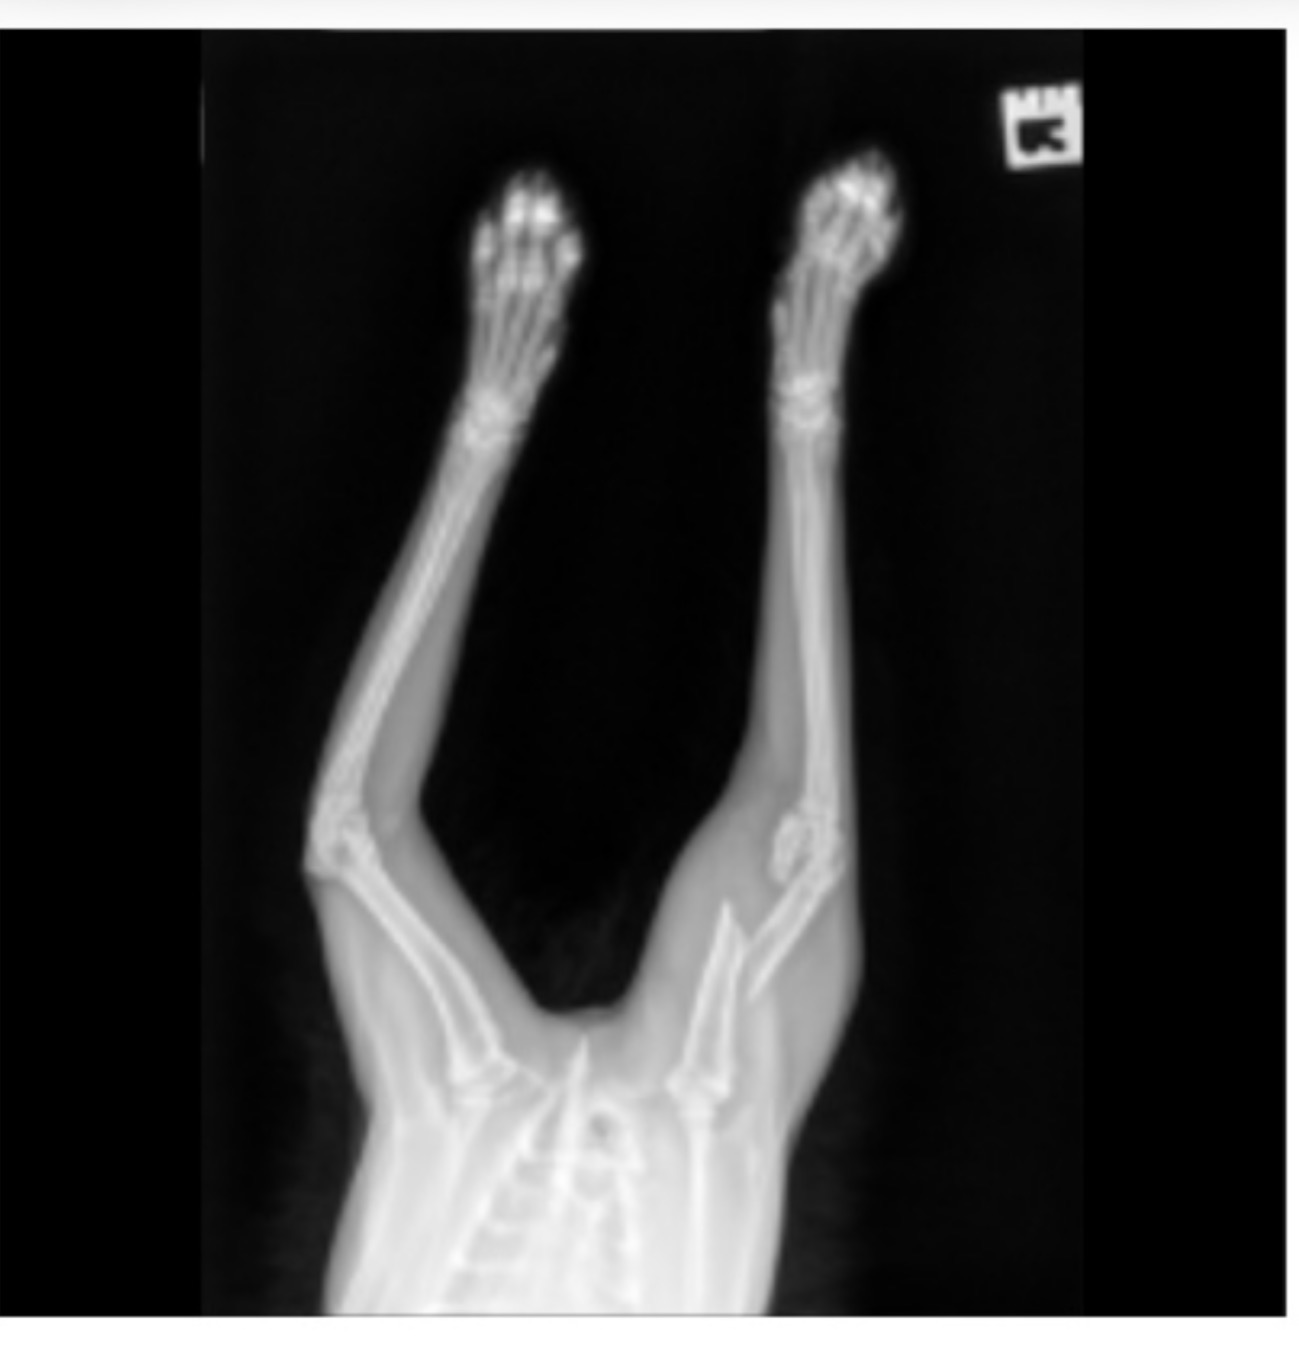

The X-rays show that Smokey Bear has suffered two significant breaks in his right forelimb:

• A closed complete displaced spiral fracture of the humeral diaphysis (the middle of the upper arm bone).

• A complete displaced fracture of the distal humerus (near the elbow joint).

Because the fractures are "displaced," the bones are no longer aligned. This means Smokey Bear requires having his front leg amputated which would increase his mobility and lessen the risk of him injuring himself .